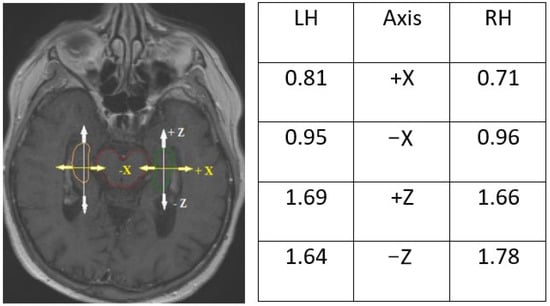

3.4. Discrepancies in Axis and Location